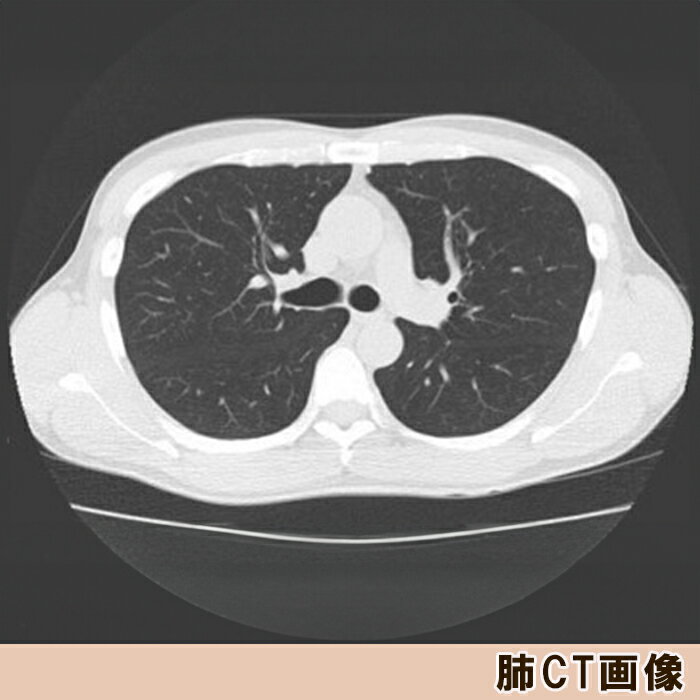

【ふるさと納税】【亀田クリニック人間ドック】肺CT検査(肺がん検診)コース 1名様(単独) [0055-0002]